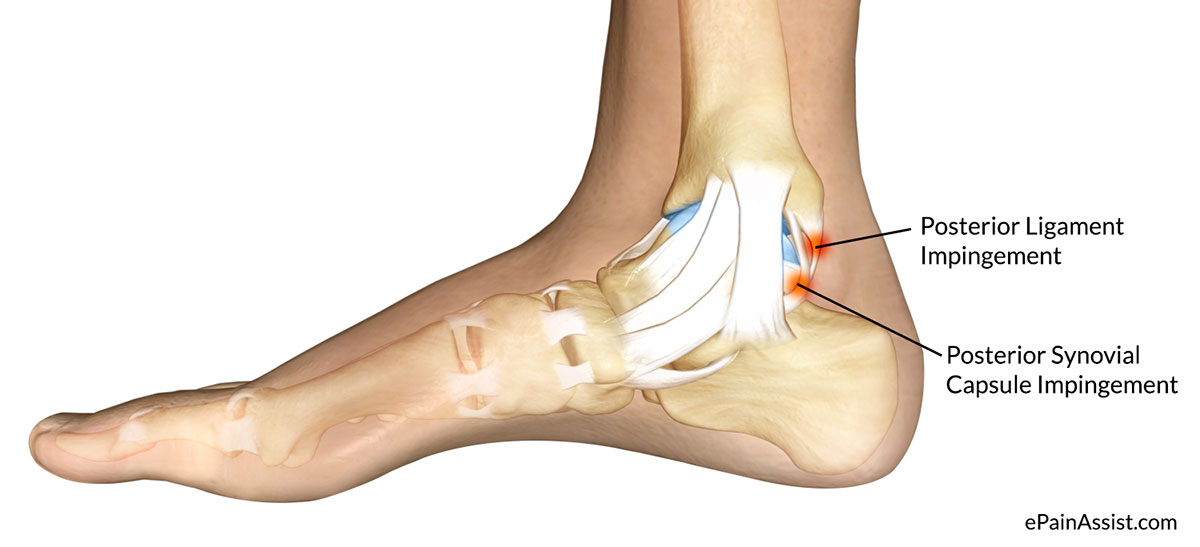

Анатомия голеностопа: Сухожилия и их строение